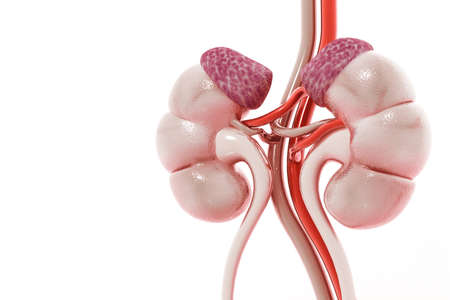

Human Kidneys Anatomical Model isolated on white background